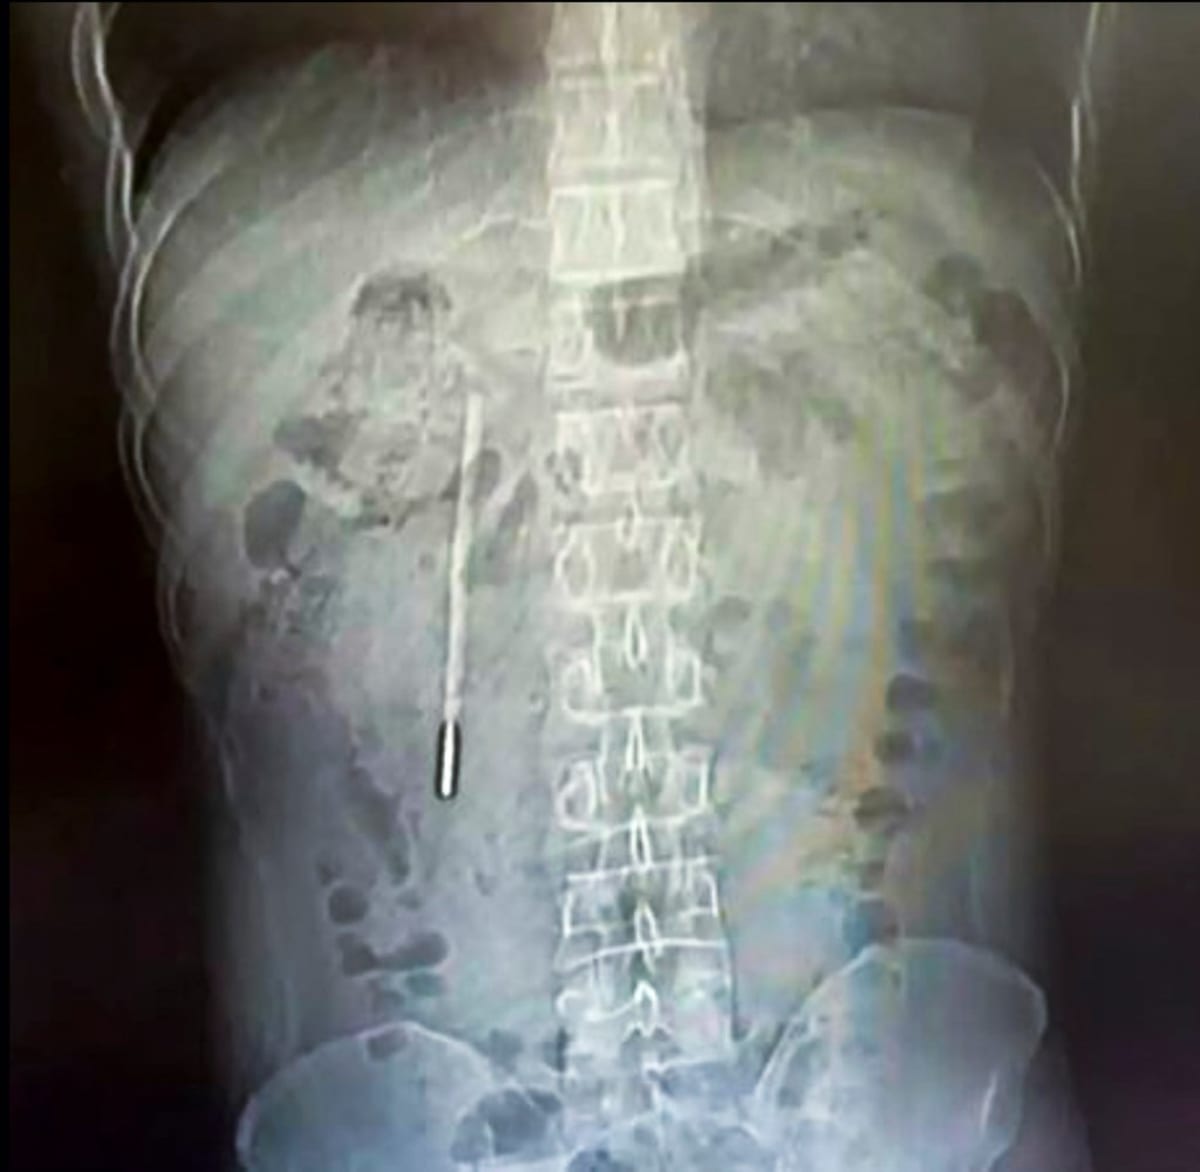

Doctors at The First Affiliated Hospital of Wenzhou Medical University ran an X-ray and spotted something unusual. A mercury thermometer was lodged in Wang's duodenum, its tip pressing dangerously against his intestinal wall.

But two decades later, the thermometer had become a serious problem. The device was positioned in a way that could cause a perforation and severe internal bleeding if left untreated.